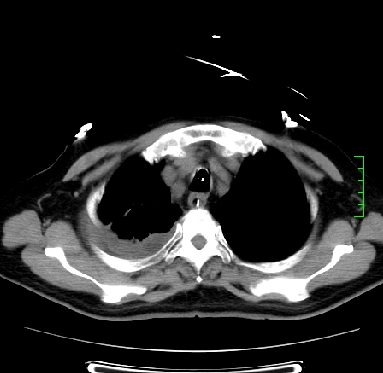

icu病人,几天都没明确诊断。m,76y,咳嗽、咳痰1周,伴气促,右胸痛入院,pe:t38.3c p135 r25 bp135/85。双肺可闻及大量湿罗音,心、腹未见明显异常。诊断:1心衰?2肺部感染?3冠心病?

9号平片

11号ct

双肺感染性病变,下叶膨胀不全,胸水,左室大。

1)两肺感染性病变(右肺下叶肺脓肿可能)。2)双侧胸腔积液,以右侧为甚。

ards,肺感染性病变,右下叶实变,双侧胸腔积液,右侧为著,叶间胸膜积液,右上肺陈旧性tb纤维灶,左室大。